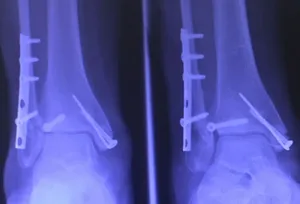

Below are x-rays of a foot pre-operatively (left) where the black line indicates and plantarflexed (downward directed) talus bone and post-surgical repair with a subtalar joint implant and lenthening of the calf muscle which allows the calcaneus (heel bone) to set underneath the talus and the implant keeps the talus from subluxing off the calcaneus and now the talus is more inline with the front of the foot (right).